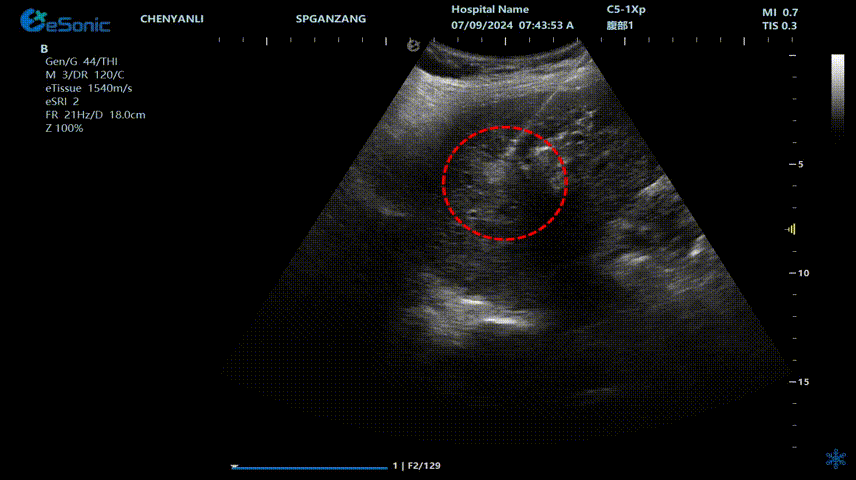

640 (2).gif

肝癌射频消融动态视频

红圈为病灶位置

640 (1) (2).gif

肝癌射频消融:全麻下彩超探头引导射频针分别植入肝右叶两个稍高回声结节,固定消融,至结节全部为强回声覆盖,覆盖良好,缓缓灼烧针道后退针。